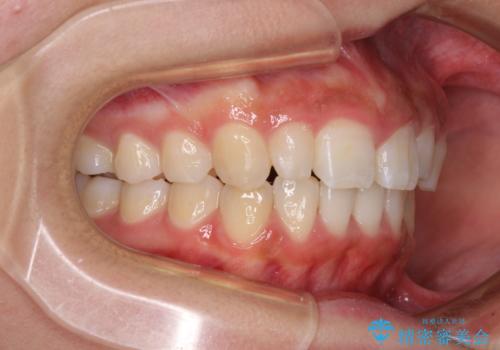

前歯のデコボコを治したい インビザラインによる矯正治療

- 前歯のデコボコ気になるとのことで来院された患者様です。

上下顎ともに歯列全体の後方移動とIPR(歯と歯の間を削る)によってデコボコが解消するように設計し、インビザラインにより治療を行うこととしました。

上顎左右前歯に矮小歯があるため、上顎の奥歯は下顎に対して相対的に前方に位置することになりました。

それでも奥歯の咬みにくさはなく、患者様には大変満足していただきました。